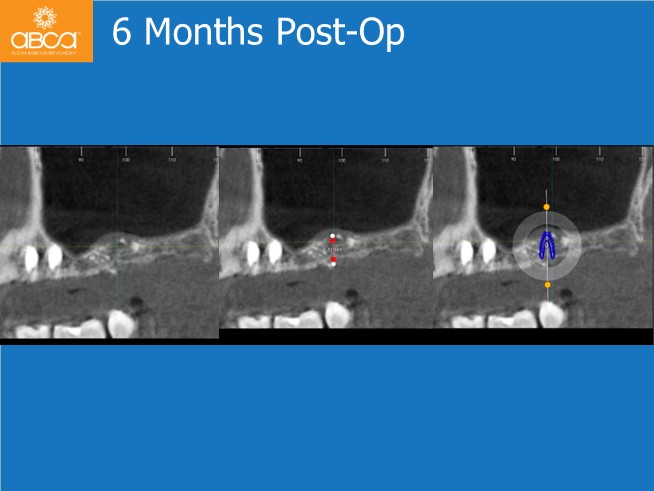

Preoperative CBCT imaging demonstrated sufficient bone volume for placement of two implants in sites #24 (12) and #25 (13), with a progressive increase in the sinus cavity in the distal region.

The surgical treatment proceeded successfully in two stages. First, the clinician placed implants in the premolar sites and performed the sinus lift. After six months, an implant was placed in site #27 (15).